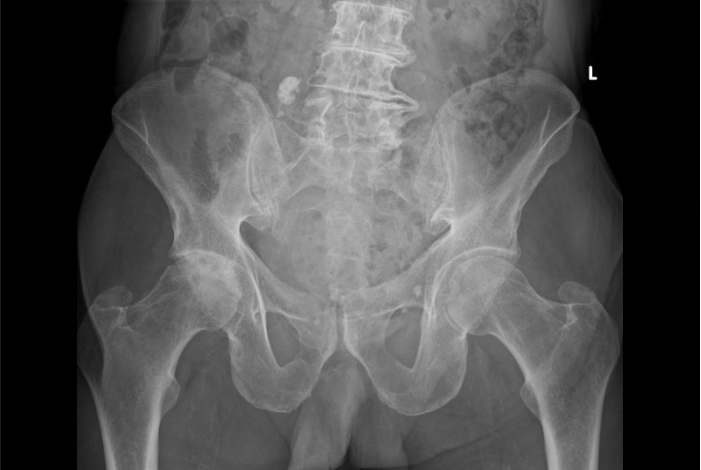

다리를 움직일 때마다 엉덩이 깊은 부위가 아프신가요?

양반다리나 계단 오르기가 힘들어지셨나요?

고관절을 감싸고 있는 연골이 나이가 들면서 점차 닳아 없어지고,

관절 간격이 좁아지면서 뼈끼리 맞닿아 염증과 통증이 생기는 질환입니다.

무릎이나 허리 통증으로 오인되어 진단이 늦어지는 경우가 많습니다.